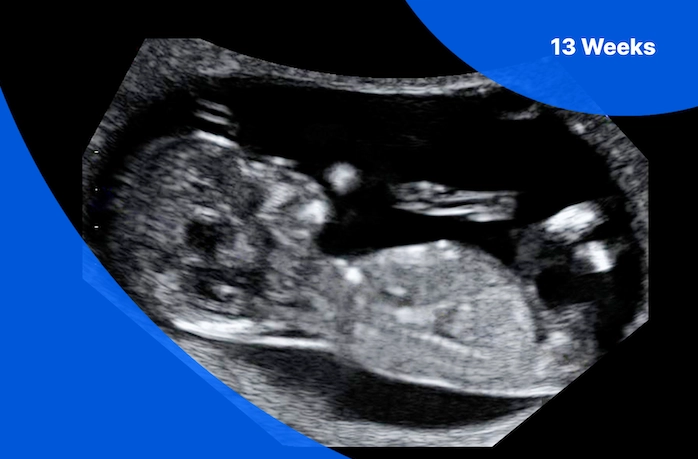

The 12-Week Ultrasound (NT Scan)

This is the big one. The nuchal translucency (NT) scan isn't just for screening; it's a wealth of reassurance. A healthy scan will show:

A wiggly, active baby. You'll see them move, maybe even suck a thumb. The heart rate will be strong, typically between 150-170 beats per minute, though a normal range can be wider (according to the American College of Obstetricians and Gynecologists, a normal fetal heart rate at this stage is between 110-160 bpm, but it's often higher early on).

All major structures present. The sonographer will check for the skull, brain, stomach, bladder, arms, legs, hands, and feet. Seeing these form correctly is a massive positive sign.

Normal nuchal translucency measurement. This is the fluid at the back of the baby's neck. A measurement within the normal range for your baby's size is a good indicator of low risk for certain chromosomal conditions.